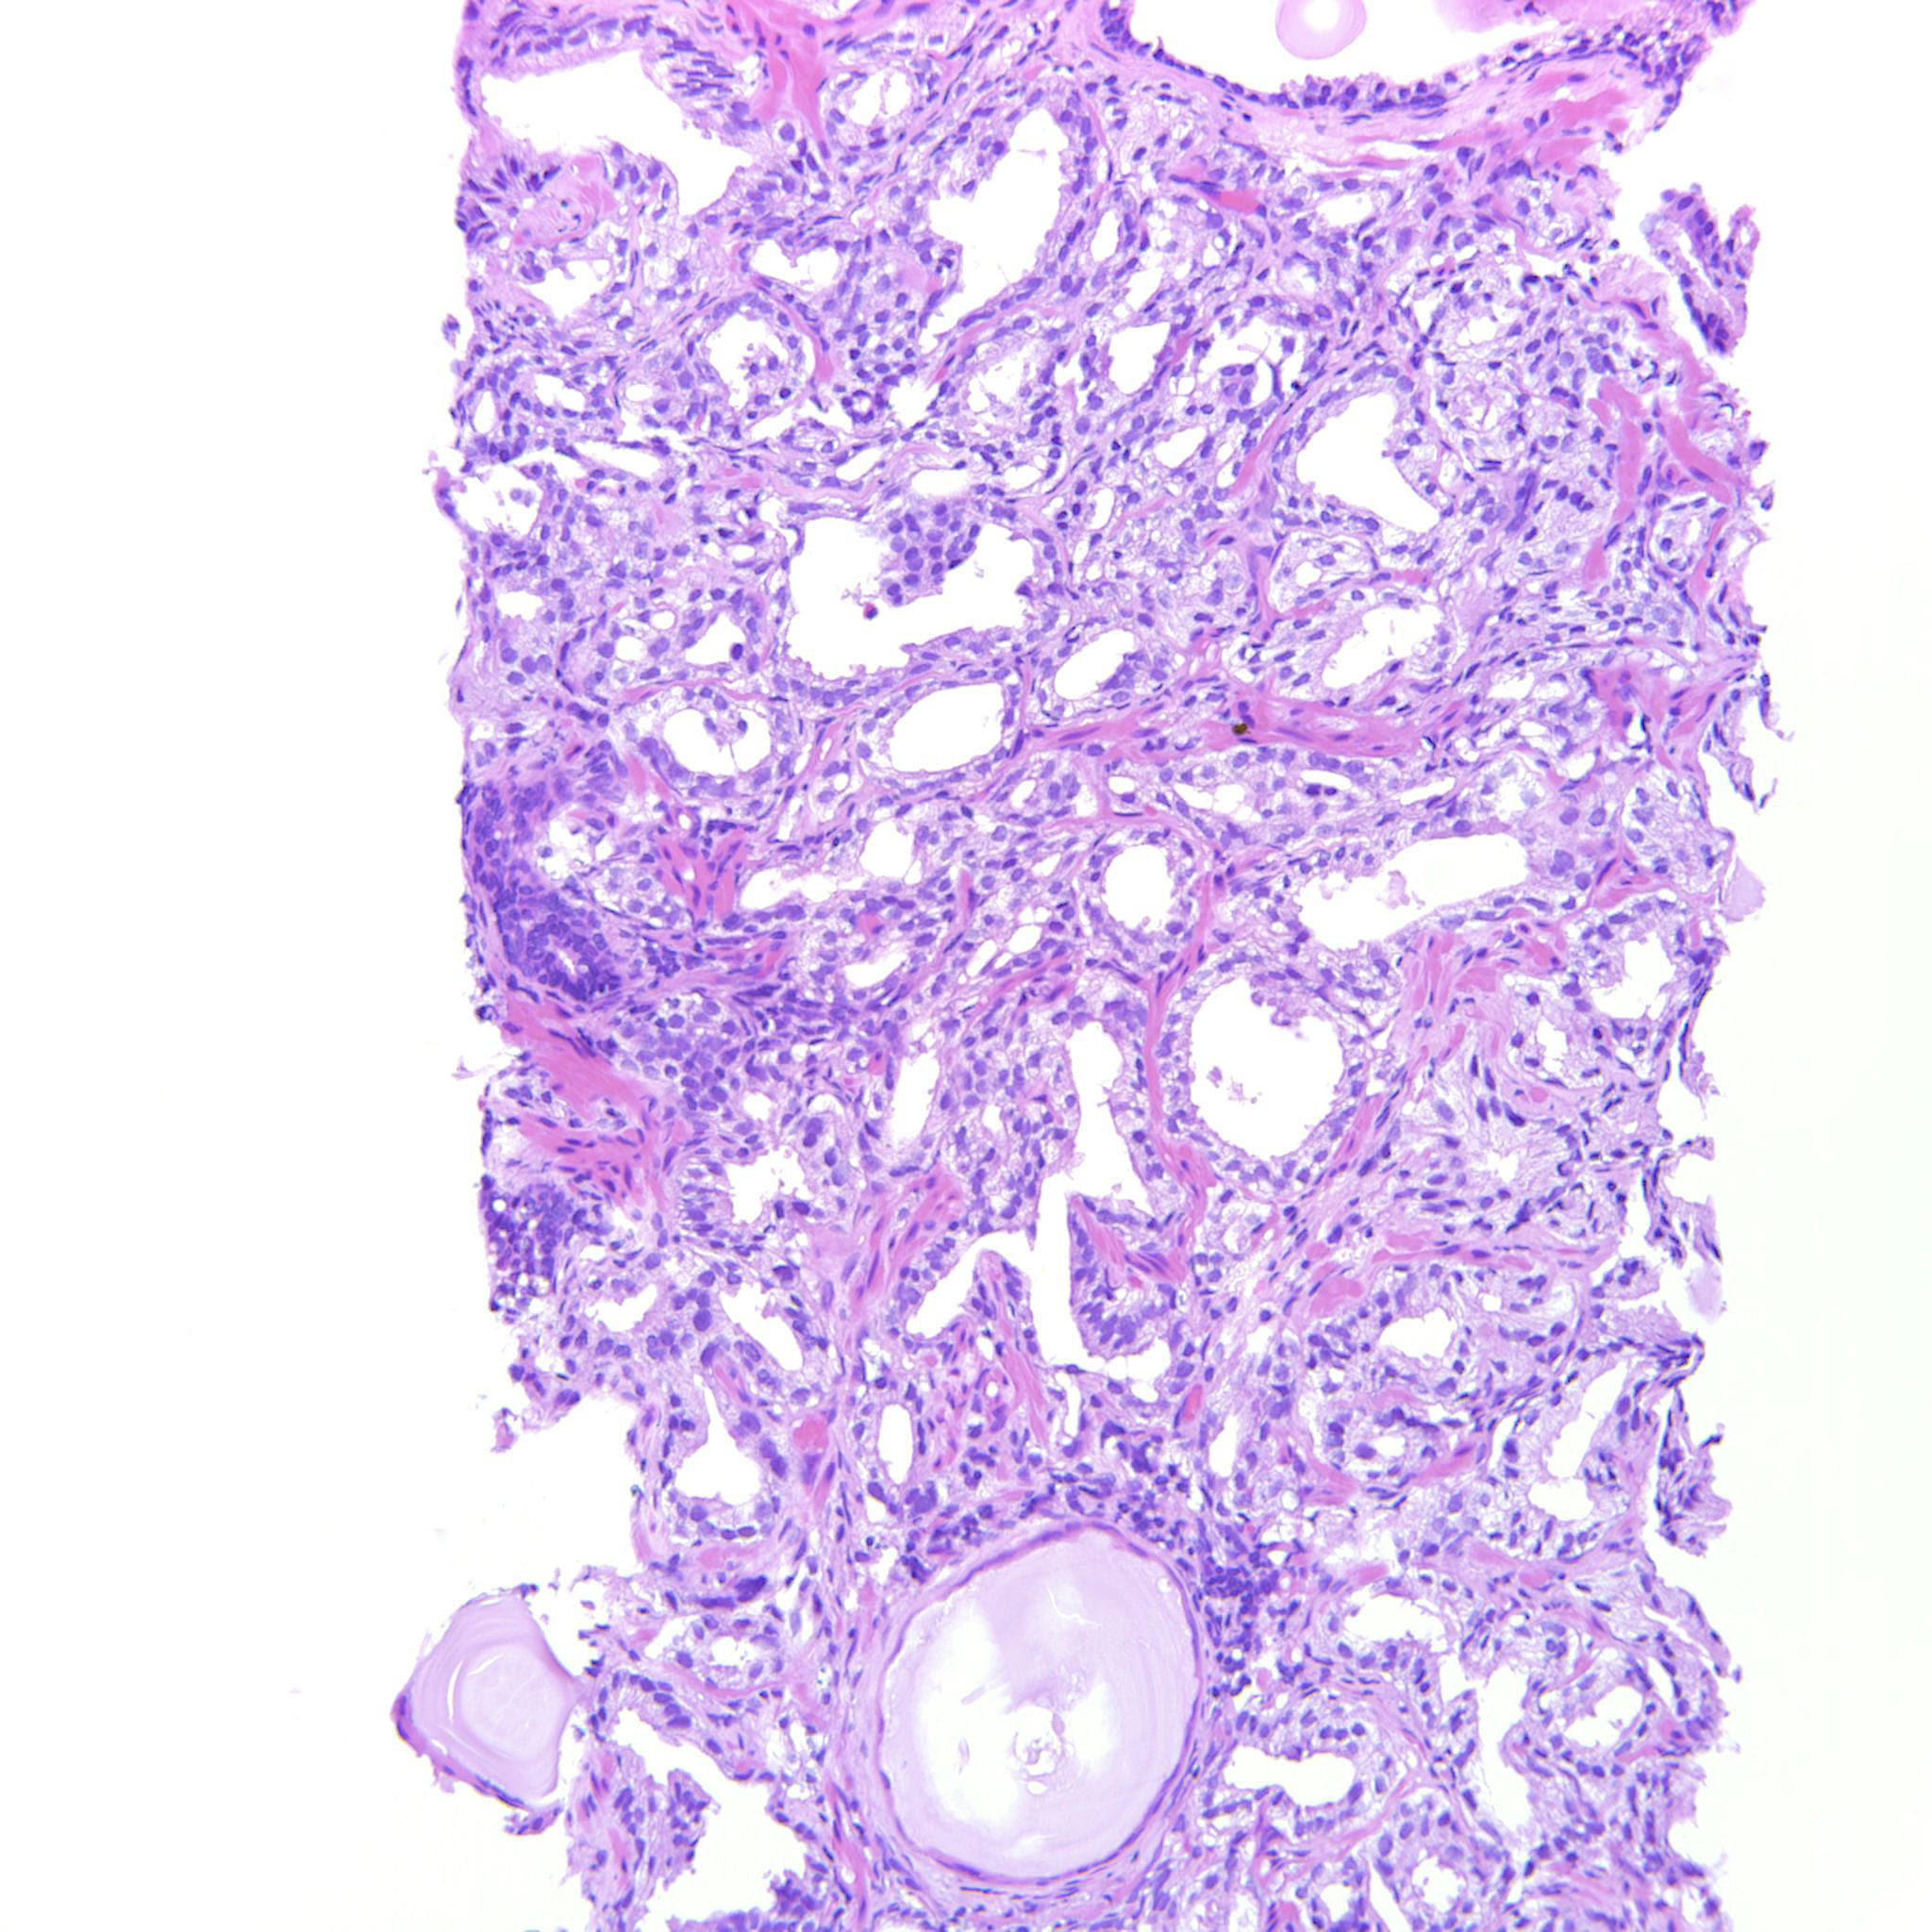

Prostate cancer grading

Case ID: 322